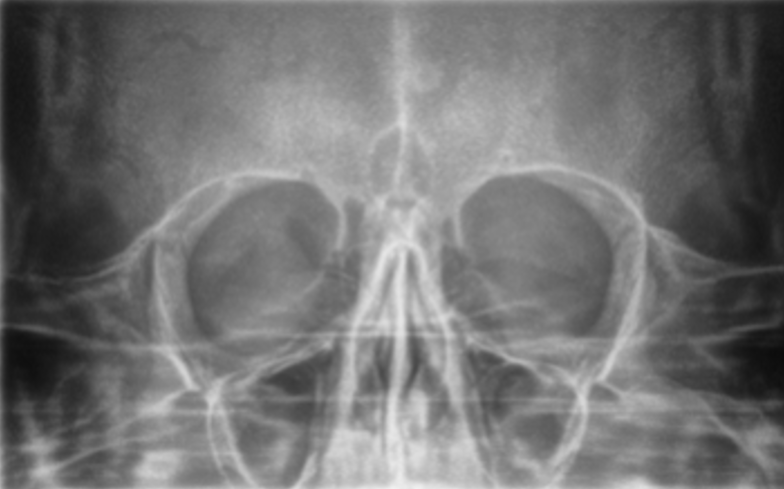

Рентген придаткових пазух носа

400 грн

Ортопантомограма (ОПТГ) потрібен щоб:

• Провести оцінку стану навколозубних тканин, верхньощелепних синусів, скронево-щелепного суглоба.